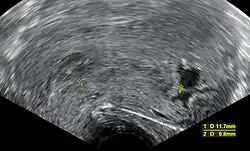

Transvaginal ultrasonography, with some products of conception in the cervix (to the left in the image) and remnants of a gestational sac by the fundus (to the right in the image), indicating an incomplete miscarriage

An incomplete miscarriage occurs when some products of conception have been passed, but some remain inside the uterus.[113] However, an increased distance between the uterine walls on transvaginal ultrasonography may also simply be an increased endometrial thickness and/or a polyp. The use of a Doppler ultrasound may be better in confirming the presence of significant retained products of conception in the uterine cavity.[114] In cases of uncertainty, ectopic pregnancy must be excluded using techniques like serial beta-hCG measurements.[114]